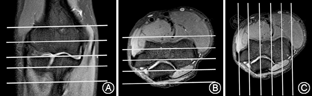

采用荷兰Philips Achieva 3.0 T超导MR扫描仪。首选肘关节表面线圈或柔线圈。儿童和青少年因肘关节体积较小可选用腕关节线圈。扫描时患者俯卧于扫描床上,患侧上肢向前伸置于头顶外上方,头向健侧倾斜,尽量远离肘关节,掌心向内侧,肘关节尽量靠近主磁场中心,如患者肘关节不能伸直,可取肘关节屈曲位,关节呈角135°左右,根据病史在病变部位贴标志。肘关节轴位扫描以肱骨下缘(肘窝)为中心,自肱骨干骺端到桡骨粗隆连续扫描(图1A),包括肱骨内外侧髁和桡骨粗隆(肱二头肌肌腱止点),冠状位扫描利用轴位定位像,平行于肱骨内外髁的连线连续扫描(图1B),矢状位扫描利用轴位定位像,垂直于肱骨内外髁的连线连续扫描(图1C)。

患者取俯卧位,肘关节尽量伸直,线圈尽量裹紧关节,行轴位、冠状位、矢状位的质子压脂序列(PD-FS序列)和冠状位T1WI序列扫描(图1)。扫描参数:PD-FS序列,TE=40~45 ms,TR=3 000~4 000 ms,层厚3 mm,层间距0.3 mm,层数12层;冠状位扫描野(FOV)120 mm×120 mm,矩阵268×205;矢状位FOV 120 mm×120 mm,矩阵268×205;轴位FOV 130 mm×130 mm,矩阵388×224。T1WI序列,TE=8 mm,TR=561 mm,层厚3 mm,层间距0.3 mm,层数12~24层;冠状位FOV 120 mm×120 mm,矩阵268×205;矢状位FOV 120 mm×120 mm,矩阵268×205;轴位FOV130 mm×130 mm,矩阵388×224。